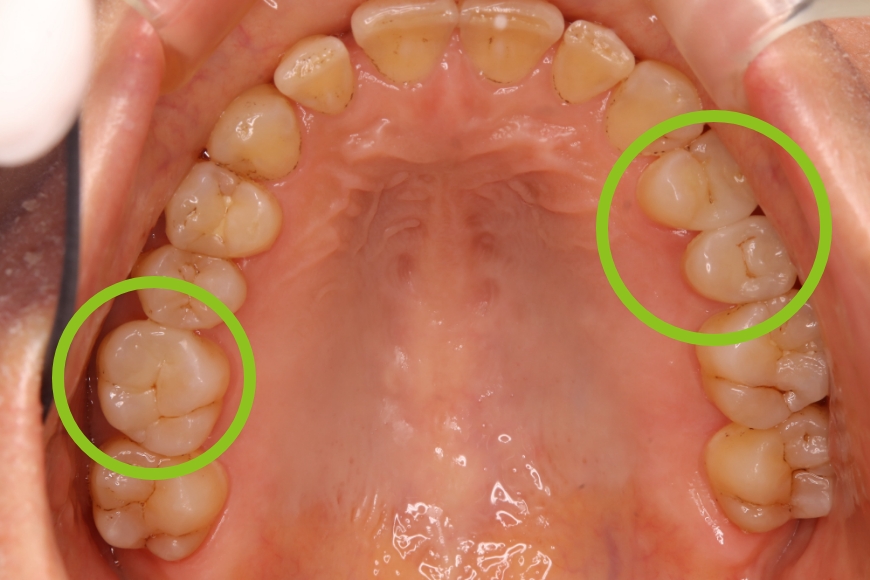

50代女性 左右の奥歯へのインプラント治療

治療前

治療後

治療内容 下の左右の奥歯が無く、食事がうまくできないことを主訴に来院されました。

左右の奥歯に2本ずつインプラント治療を行いました。奥歯でしっかりと噛めるようになりました。

治療期間・回数 治療期間:約6ヶ月

通院回数:10回程度

1,760,000

(1本440,000円×4本分。時期や手法により異なる場合があります。)

副作用・リスク ・インプラント埋入手術直後は、不快感、痛みを感じることがあります。

・下顎のインプラントは下歯槽神経に障害を及ぼした場合、数か月の知覚異常が生じる場合があります。

・インプラント周囲炎(インプラントの歯周病)などのトラブルを防ぐため、定期的なメンテナンスを行う必要があります。